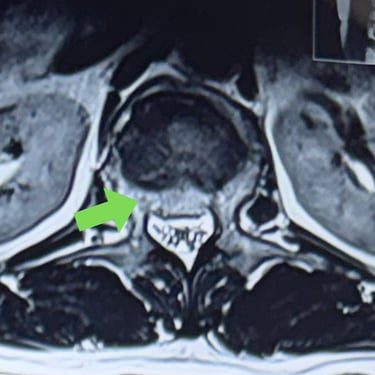

Fractura vertebral lumbar – Artrodesis con tornillos transpediculares (FTP).

La fractura vertebral lumbar es una lesión que puede comprometer la estabilidad de la columna y generar dolor, deformidad o déficit neurológico. En casos seleccionados, el tratamiento quirúrgico mediante artrodesis con tornillos transpediculares (FTP) permite una fijación firme de las vértebras afectadas, restaurando la alineación y brindando estabilidad inmediata. Esta técnica reduce el dolor, previene el desplazamiento vertebral y protege las estructuras neurológicas. La intervención oportuna, junto a una adecuada rehabilitación, favorece una recuperación funcional segura y mejora significativamente la calidad de vida del paciente.